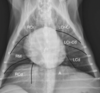

Identify the labeled structures

A = right atrium B = left atrium C = right ventricle D = left ventricle